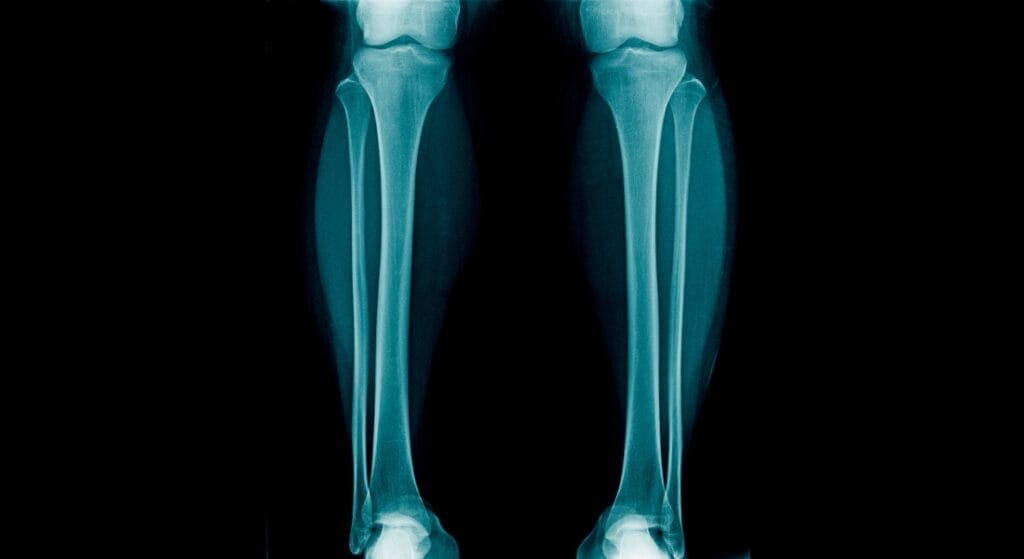

• X-quang: Giúp phát hiện nứt xương, gãy xương, hoặc tổn thương cấu trúc xương chày.

x-quang xương ống chân